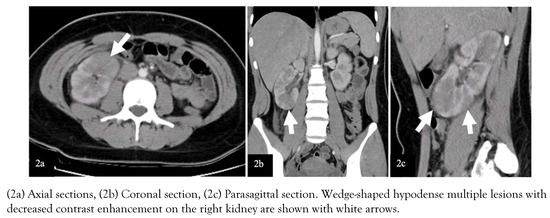

Due to the acute abdomen clinical finding in Case-2 and the significant CVA tenderness in both cases (bilateral in Case-1 and unilateral in Case-2), contrast-enhanced abdominal computed tomography (CT) was performed for differential diagnosis. In Case-1, nonhomogeneous hypodense mass-like lesions with decreased contrast enhancement in both kidneys were detected (Figure 1). In Case-2, a similar lesion was seen in the lower pole of the right kidney (Figure 2). Both cases were diagnosed with AFBN since these lesions were specific for it.

Figure 2.

Images of contrast-enhanced abdominal CT of Case-2.

Costovertebral angle tenderness is one of the specific indicators for kidney pathology and is often seen in acute pyelonephritis [12]. However, it may present in other diseases such as nephrolithiasis, kidney abscess, vesicoureteral reflux, obstructive pathologies of the urinary tract, retrocecal appendicitis, retroperitoneal abscess [13]. In a patient presenting with fever and CVA tenderness, the clinician should consider first upper UTI, among other diagnoses. In selected cases, imaging techniques can be used for differential diagnosis. Herein, due to the presence of CVA tenderness, we performed contrast-enhanced CT imaging, which showed hypodense wedge-shaped kidney lesions indicating AFBN (Figure 1 and 2) [14].

Early diagnosis and effective treatment are essential in terms of preventing renal scars and morbidity such as hypertension, proteinuria, and renal failure [18]. The diagnosis of AFBN is based on radiologic examinations. In many cases, there is no finding on kidney ultrasonography (USG), although it may show nephromegaly, focal lesions with poorly defined irregular margins. Contrast-enhanced abdomen CT is the gold standard imaging technique for the diagnosis of AFBN. Herein, both cases had no finding on kidney USG. The lesions were observed on CT as the typical wedge-shaped, poorly defined hypodense lesions after contrast-medium administration [14]. The DMSA scan of the kidneys may help in the diagnosis of AFBN and the detection of renal scarring during follow-up [19]. In Case-1, the diagnosis of AFBN was supported with the DMSA scan. In Case-2, the DMSA scan in follow-up shows no scars indicating the effective treatment.